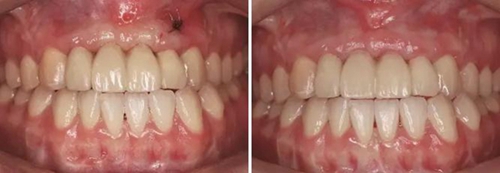

③患者試戴個(gè)性化氧化鋯基臺(tái),檢查基臺(tái)就位情況,咬合狀況,基臺(tái)邊緣位于齦緣下<1mm,試戴氧化鋯基底,確認(rèn)基底就位良好,邊緣密合,完成永久修復(fù)體的制作??趦?nèi)戴入氧化鋯基臺(tái)后,扭矩扳手加力至30N后,聚四氟乙烯封閉螺絲通道,樹脂封孔。試戴全瓷修復(fù)橋體,檢查冠邊緣與基臺(tái)邊緣緊密接觸,與周圍軟硬組織相協(xié)調(diào),確認(rèn)鄰接以及修復(fù)體顏色良好。調(diào)整咬合,靜態(tài)咬合:正中咬合時(shí)后牙區(qū)均勻接觸,輕咬合時(shí)前牙區(qū)無(wú)接觸,重咬合時(shí)輕接觸,無(wú)牙合干擾或早接觸;動(dòng)態(tài)咬合:側(cè)方運(yùn)動(dòng)時(shí)尖牙引導(dǎo)或前牙組牙功能的交錯(cuò)保護(hù)牙合,前伸運(yùn)動(dòng)是切牙引導(dǎo)牙合,工作側(cè)和非工作側(cè)無(wú)牙合干擾。咬合調(diào)整完畢后高度拋光,口外用硅橡膠制備預(yù)粘接代型,超聲振蕩修復(fù)體,消毒后使用自粘接樹脂水門汀于口外預(yù)粘接并戴入口內(nèi),使用牙線去除多余粘接劑。拍攝X線片,確認(rèn)基臺(tái)和牙冠完全就位。

圖37 戴入全瓷修復(fù)體局部舌側(cè)觀 圖38 永久修復(fù)后微笑

圖39 永久修復(fù)后大笑

3、通過制作個(gè)性化轉(zhuǎn)移桿,將種植體周圍軟組織的形態(tài)輪廓精確地復(fù)制并轉(zhuǎn)移到模型上,個(gè)性化制作的氧化鋯基臺(tái)及全瓷修復(fù)體,生物相容性及美學(xué)效果良好,患者對(duì)最終修復(fù)效果滿意。